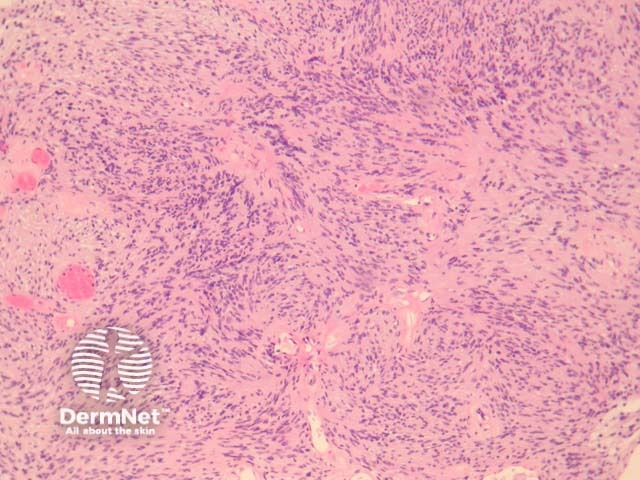

In schwannoma, sections show an encapsulated well-circumscribed lesion beneath the uninterrupted epidermis. The tumour is composed of different areas composed of different cellular densities. More cellular areas (Antoni A, figure 1) are composed of a haphazard arrangement of bland cells with spindled and oval nuclei. Loose, less cellular areas (Antoni B, figure 2) are composed of a loose oedematous and mucinous stroma with fibrillar collagen. The vessels are prominent and often surrounded by a dense sclerosis.

Figure 1